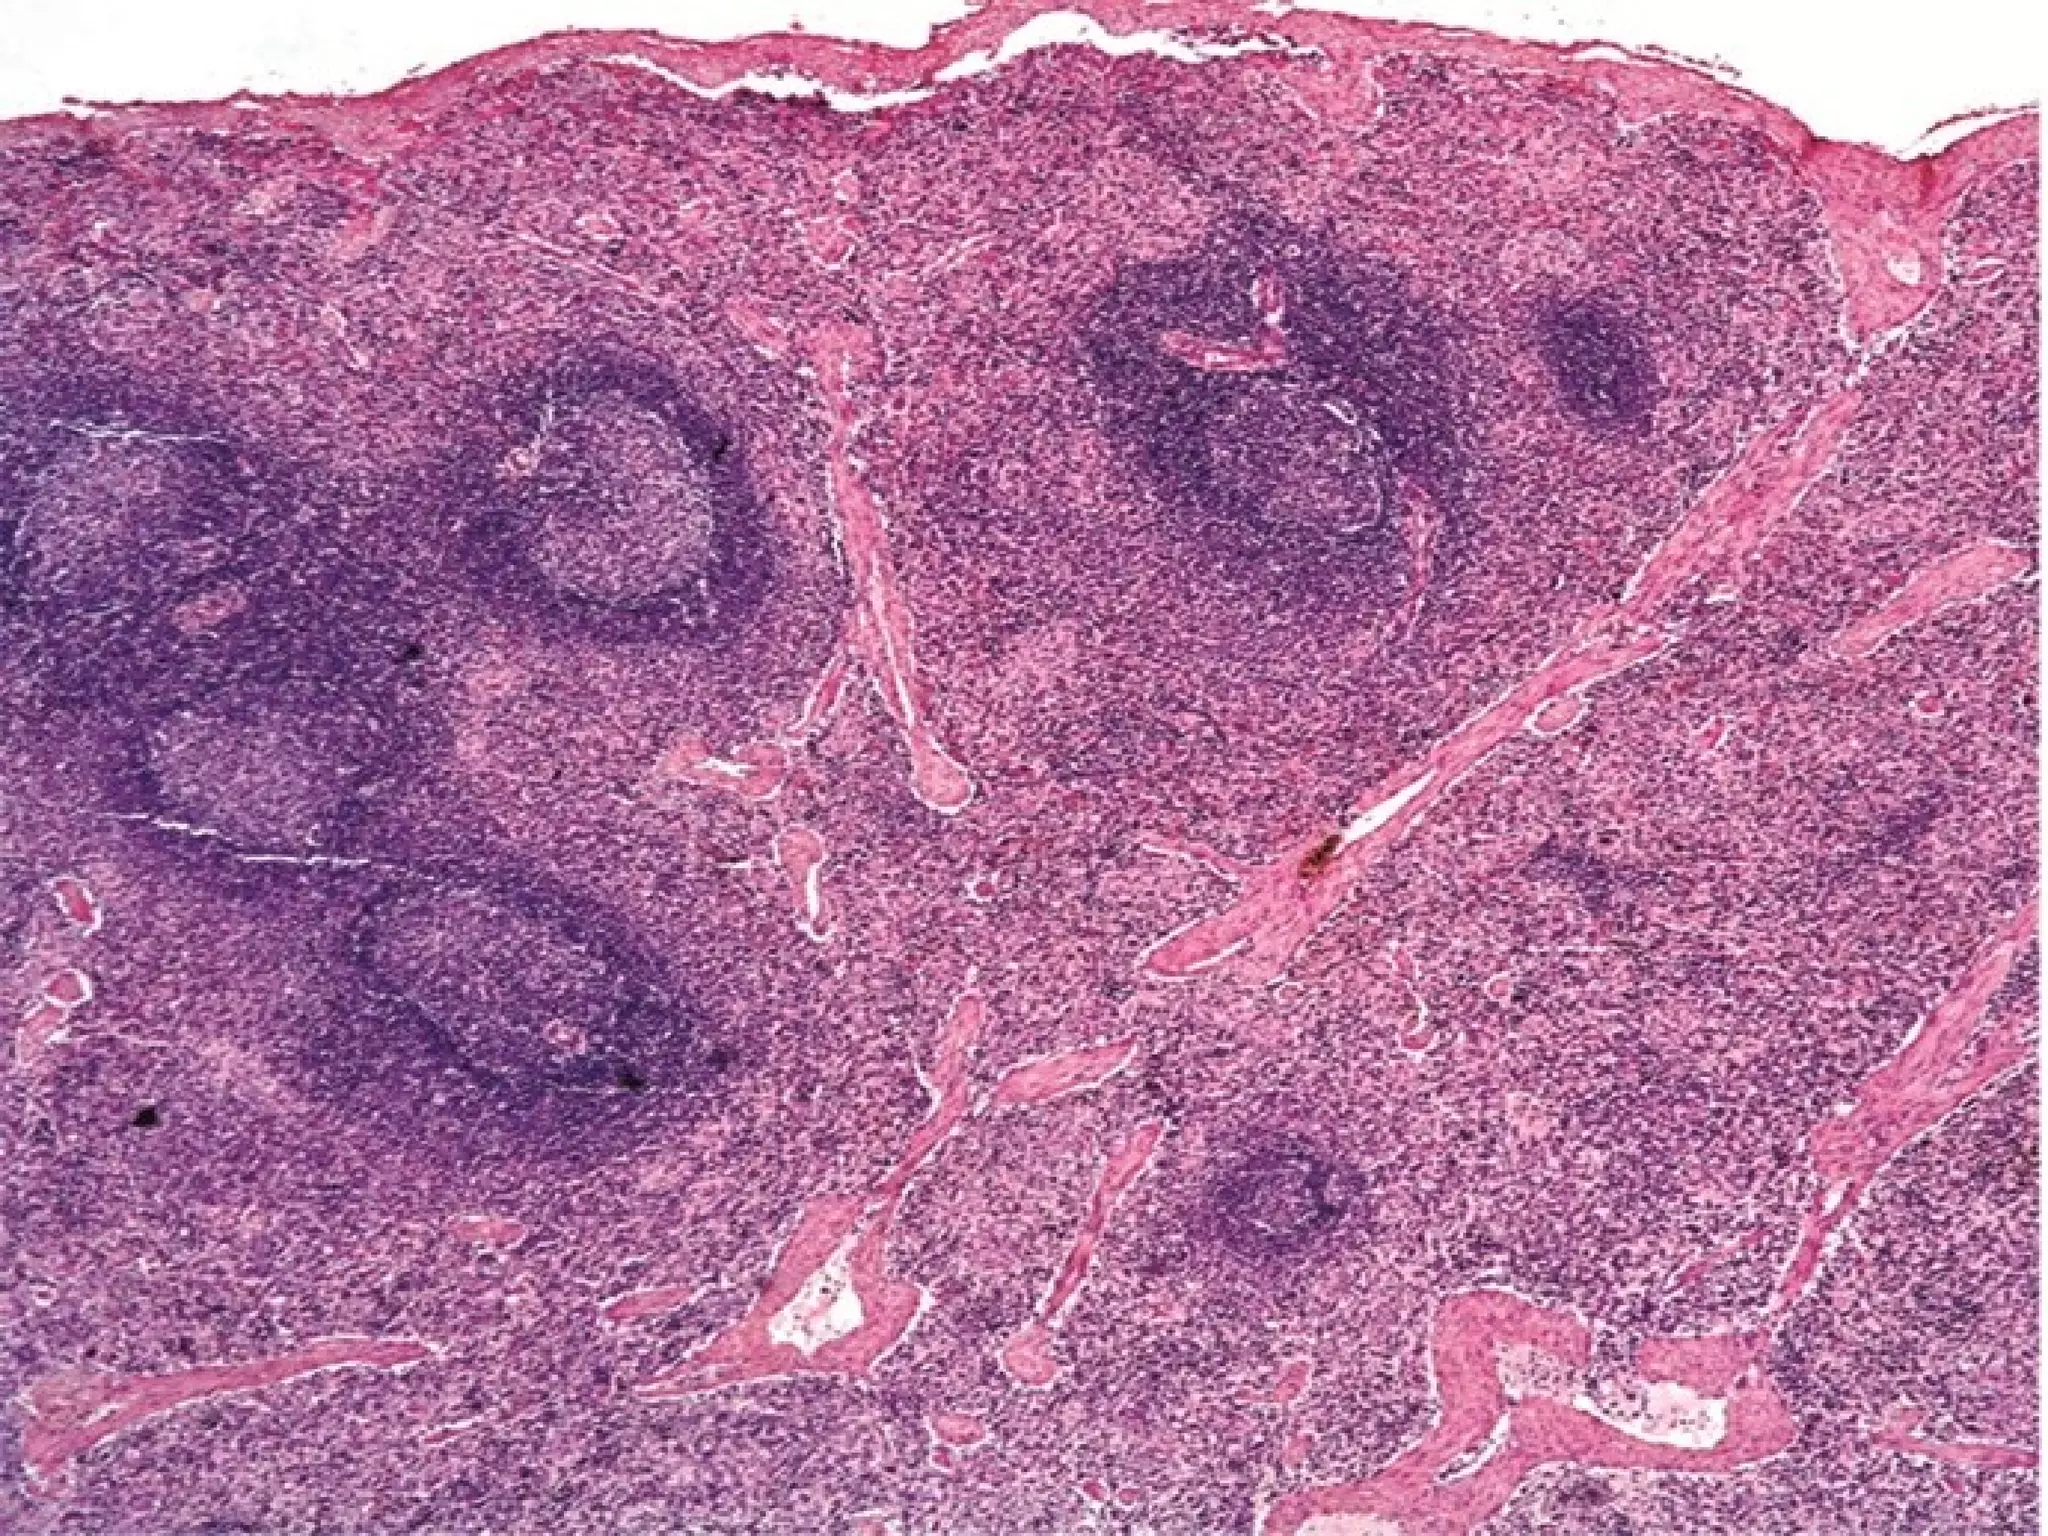

This document outlines several human body systems including the vascular, lymphatic, respiratory, digestive, and endocrine systems. It describes the trachea and lungs in the respiratory system, the oral cavity and digestive glands in the digestive system, and mentions the parotid, pancreas, and classic hepatic lobule in relation to the digestive system and endocrine glands.